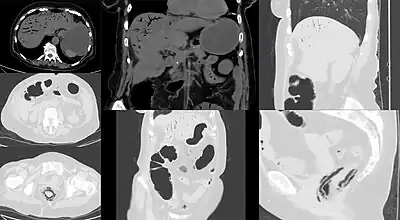

CT image showing mesenteric ischemia with pneumatosis intestinalis and gas in mesenterial and liver veins

Computed tomography (CT scan) is often used.[29][30] The accuracy of the CT scan depends on whether a small bowel obstruction (SBO) is present.[31]

Early findings on CT scan include:

• Intestinal mesenteric edema[29]

• Bowel dilatation[29]

• Bowel wall thickening[29]

• Intestinal mesenteric stranding[32]

• Evidence of adjacent solid organ infarctions to the kidney or spleen, consistent with a cardiac embolic shower phenomenon

In embolic acute intestinal ischemia, CT-Angiography can be of great value for diagnosis and treatment. It may reveal the emboli itself lodged in the superior mesenteric artery, as well as the presence or absence of distal mesenteric branches.[18]

Late findings, which indicate dead bowel, include: